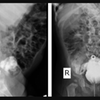

A história veiculada pelo Daily Mail diz que a radiografia mostrou o objeto alojado no cólon do menino, mas sem provocar dor. Os médicos precisaram usar um total de seis ferramentas diferentes para retirar a bola de golfe do intestino do adolescente, incluindo uma ventosa, uma rede médica, uma pinça de quatro pinos e um cateter de balão.

Depois de duas horas sem sucesso no procedimento, os médicos decidiram esperar que objeto saísse de forma espontânea. No entanto, os novos exames de raio-X feitos no dia seguinte, mostraram que a bola seguia presa no mesmo local.